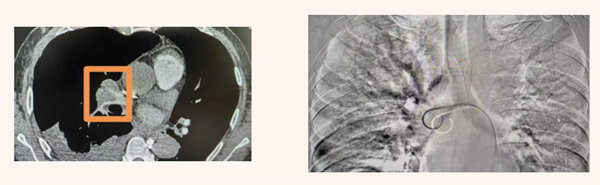

患者68岁男性,因“胸闷、腹胀、进行性呼吸困难”辗转多家医院,均以“胸腹水原因待查”进行治疗,效果欠佳。为求明确诊断,患者来到宝鸡市人民医院呼吸与危重症医学一科。入院次日,患者病情骤然加重,急诊检查提示“左下肢深静脉血栓形成”及“急性肺栓塞”,生命垂危。医院立即启动绿色通道,介入团队迅速为患者施行“肺动脉内碎栓及下腔静脉滤器植入术”,成功化解了眼前的致命危机。

然而,肺栓塞的紧急处置只是第一步。呼吸与危重症医学一科团队并未停止思考:肺栓塞的根源是什么?患者持续存在的胸腹水究竟由何而起?在科主任带领下,团队多次组织科内疑难病例讨论,沿着“肺栓塞确诊—溯源求因”的严谨临床思维路径,对患者所有病史、检查资料进行地毯式复盘与分析。大家将目光从胸腔逐步聚焦到腹腔,发现其腹膜存在弥漫性异常增厚伴结节,这一关键线索成为破案突破口。

为进一步明确诊断,团队与超声医学科、病理科紧密协作,为患者实施了“超声引导下腹膜穿刺活检术”。病理结果提示:镜下查见异型细胞,符合恶性间皮瘤的免疫表型特征。 至此,最终诊断揭晓:弥漫性恶性腹膜间皮瘤(DMPM)。